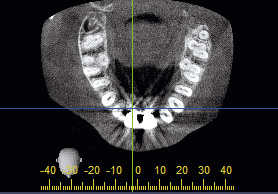

2/26 - CT scan reveals major bone loss in frontal maxillaBone augmentation in aesthetic zone with maxgraft® bonering - Dr. A. Patel